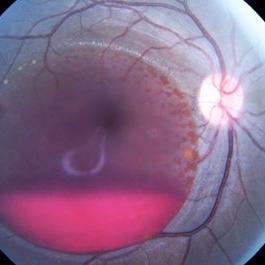

Choroidal Detachment

Sep 10 2014 by Mehul A Shah

A male patient 5-years-old presented to outdoor and found to have retinal detachment with choroidal detachment following blunt trauma

Photographer: Drashti Netralaya,Dahod

Imaging device: FF 450

Condition/keywords: choroidal detachment